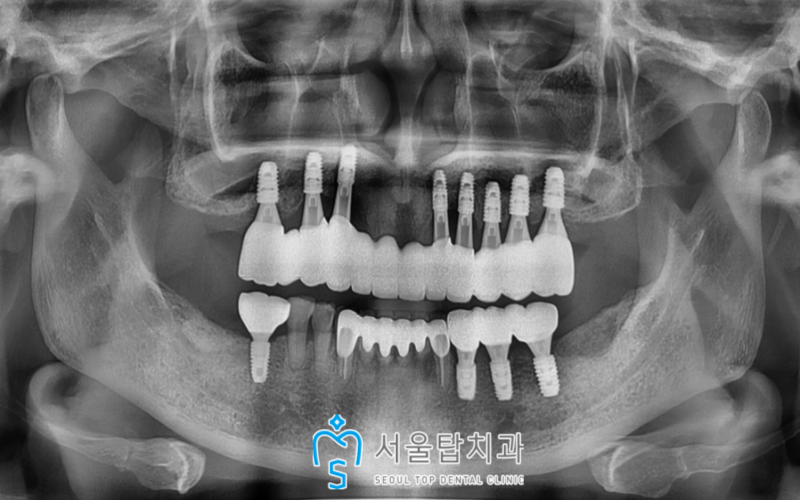

임플란트와 치조골이

단단하게 결합될 때까지

충분한 시간을 가진 뒤

골유착이 잘 되었다고 확인되었을 때

최종 보철물까지 진행하여

임플란트를 성공적으로 마무리해드린

치료 종결 후 파노라마 사진입니다!

🦷 치료전 🦷

서울탑치과 임플란트

🦷 치료후 🦷